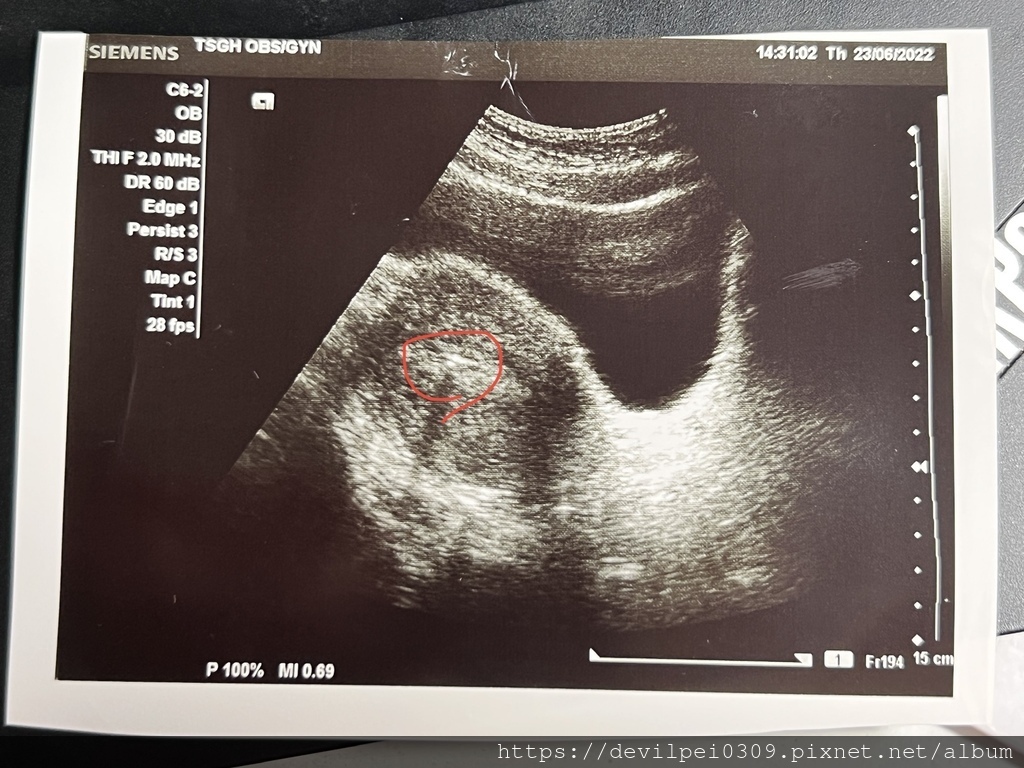

先打油針~打完後才開始植入,我是兩點植入,醫生交代12點過後我就不能上廁所,主要是為了讓膀胱漲起來,照肚皮超音波才能看到。

植入會搭配超音波找位置,確認後位置後才放入,過程約10分鐘左右吧!結束後需要躺個10分鐘之類的~然後就可以下床走動了。

想不到我竟然會在這個時候~獲得第一章超音波照! 仔細看的話~中間有兩個小點~就是植入的兩個胚胎

醫生有交代不可以【提重物】不要使用【蹲式馬桶】,因為會造成腹壓